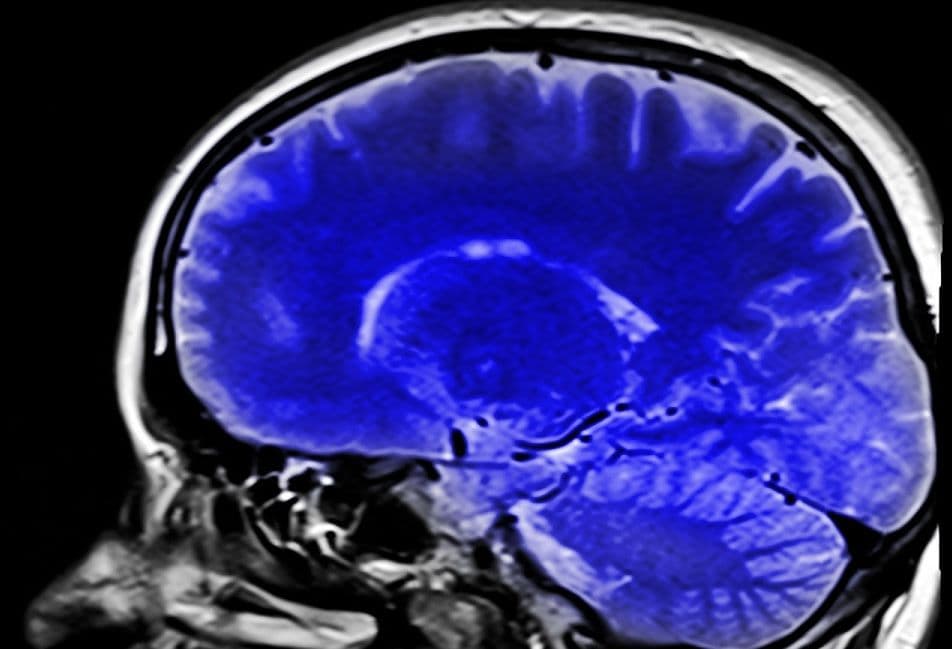

Mr Brain brengt hersenen beter in beeld

In het project ‘MR Brain’ wordt gewerkt aan een snellere en kwalitatief hoogwaardige MRI van de hersenen. Bij de huidige technologie worden neurologisch onderzoek en diagnose belemmerd door lage beeldresolutie en lange scantijden. In het project wordt een serie high-tech producten samengebracht tot één hard- en software product (plug ’n play). Het consortium Stichting Katholieke Universiteit- RU (Nijmegen), MR Coils B.V. (Zaltbommel), Screenpoint Medical B.V. (Nijmegen) en Stichting Katholieke Universiteit- Radboudumc (Nijmegen) ontvangt hiervoor een totaal subsidiebedrag van € 1.980.482 de totale kosten bedragen € 4.951.204.